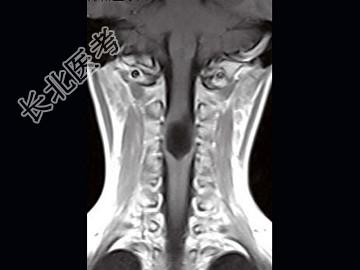

- 单项选择题女,9岁, 颈部疼痛、活动受限2个月,MRI检查如图, 最可能的诊断为 ( )